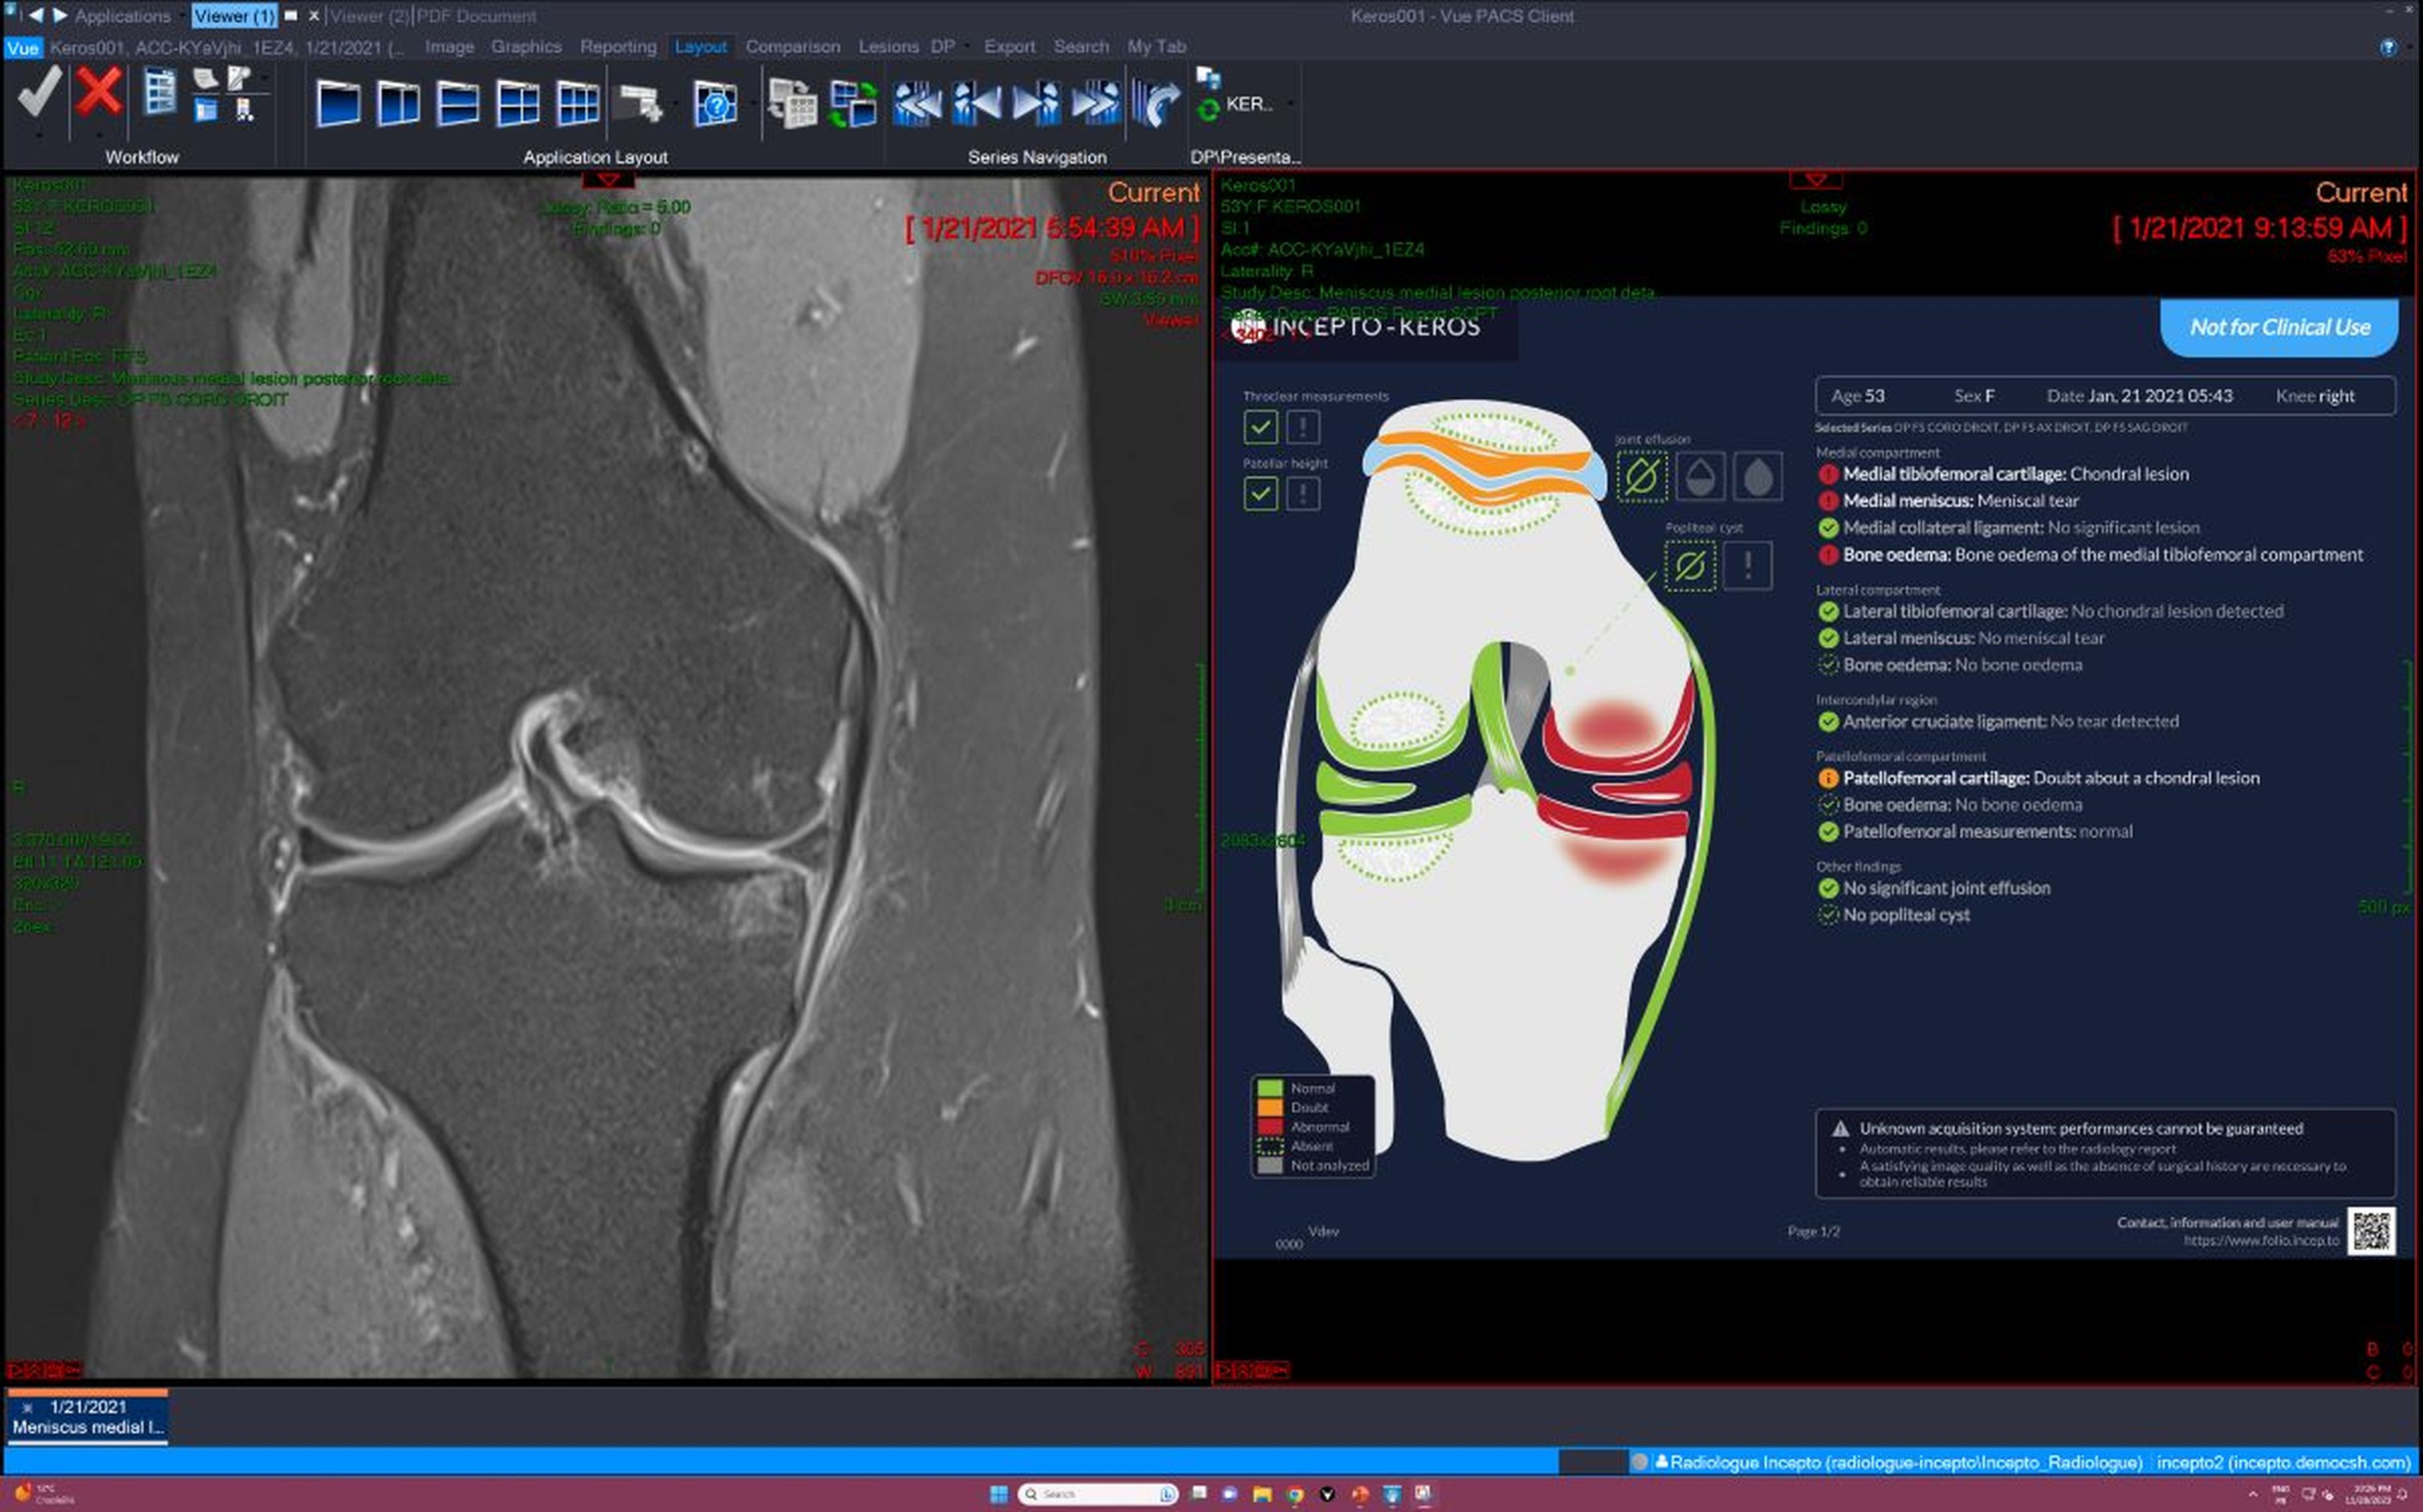

El acuerdo supondrá para estos centros la implantación de la IA en la rutina diaria de diagnóstico por imagen y detección de patologías, así como la optimización los exámenes médicos por imagen a través de resonancia magnética, siempre con la última palabra del facultativo.

El objetivo es detectar enfermedades y lesiones con mayor precisión, eliminando, como explica la empresa en un comunicado, "el sesgo humano", si bien subrayan que "la labor de los profesionales seguirá siendo fundamental: todo informe elaborado por la IA debe ser suscrito por ellos".

Jomier se detiene también en el servicio de la IA en urgencias por su especial relevancia para esa primera criba donde se dilucida si, por ejemplo, hay rotura o no de un hueso, y así priorizar e incluso dar de alta al paciente antes de tener que entrar en toda una rueda de chequeos que serían innecesarios. "Integrada fuertemente en el flujo de trabajo, la IA puede ahorrar tiempo al médico y al paciente", vaticina el CEO.

A partir de ahí, explica Jomier, el siguiente paso es desarrollar la IA para las enfermedades cerebrales y, finalmente, "llegar al 80% de todos los procedimientos de imagen", tanto para resonancia magnética (cubren por ahora el 50%), como tomografía computarizada (actualmente cubren el 20%). En rayos X, mamografías y radiografías convencionales ya cubren el 100%.